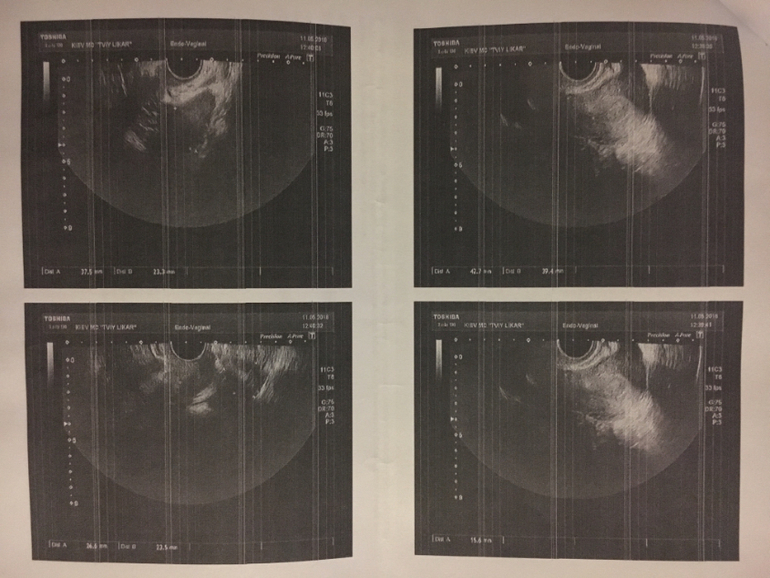

Гиня - душка. По итогу: сказала, что матка беременна, никаких отклонений по яичникам, трубам и в самой матке не увидела, пя тоже не видно (ну то понятно). Эндометрий «пышный», так она его назвала)) Так ли это? О желтом теле ничего не написано, а я с трясущимися коленками и позывами к избавлению от завтрака и магне б6 завтыкала спросить.

А вот и результаты

На описании узи опечатка в дпм))